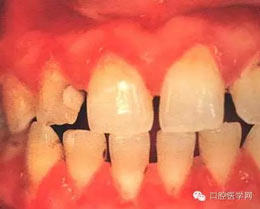

(四)壞死性齦炎:為局限的或普遍的潰瘍形成,牙間乳頭破壞,并伴有纖維蛋白性壞死。

(五)牙周炎:為牙周軟組織喪失及不規(guī)則骨破壞,可有明顯的疼痛。(早期)牙周炎軟組織損害呈火山口樣。